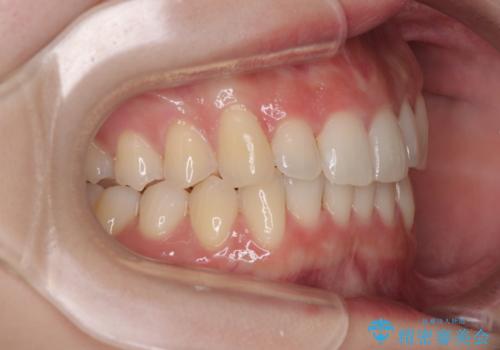

前歯が隠れるほどのデコボコをインビザライン矯正できれいに整える

マウスピース矯正特有の、奥歯が噛みにくくなるという現象の解消に少し期間をいただきましたが、日々の装着時間を遵守していただき、綺麗な歯列に整えることができました。